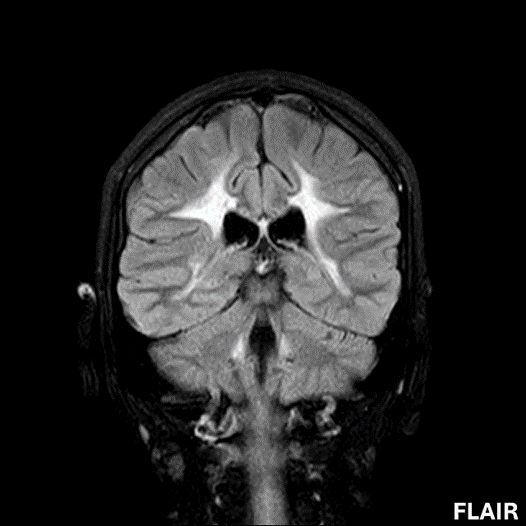

- A) Aksiyel T2A ve koronal T2A sekanslarda sentrum semiovale, korona radiata ve bazal ganglionlar düzeyinde bilateral frontoparietal derin periventriküler beyaz cevherde birleşme eğilimi gösteren hiperintens gliotik sinyal değişiklikleri (oklar) ve aksiyel T2A serilerde servikal spinal kordda posterior kolonda, lateral kesimlerde sinyal artımları (oklar) izlendi.

- LBSL, karakteristik radyolojik özelliklere sahiptir. MRG’de tipik olarak bilateral ve simetrik beyaz cevher sinyal değişiklikleri görülürken, subkortikal U lifleri, internal kapsülün posterior kolları, trigeminal sinir traktları, serebellum, korpus kallozumun spleniumu, medulla oblongata ve omurilikteki dorsal kolonlar ile lateral kortikospinal traktlar genellikle korunur.

- Etkilenen bölgelerde T1’de hipointens, T2/FLAIR’da hiperintens sinyal değişiklikleri izlenir. DWI’de lezyonların periferinde kısıtlı difüzyon görülebilir. MRS’de beyaz cevherde laktat artışı saptanabilir, ancak bu her hastada mevcut değildir.